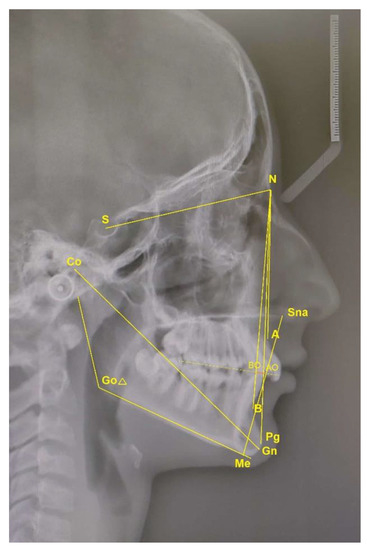

The fixed sagittal guidance (FSG) appliance is a fixed orthodontic appliance bonded on both upper molars, manufactured of a crown (cobalt-chromium alloy) and the occlusal inclined plane of SR Chromasit material (pressure/heat-curing micro filled veneer material) (Figure 3). Crowns (Figure 4) were produced using a scanner (to import physical data about the teeth into the computer) and 3D computer design and a specific method of selective laser melting (SLM) (MLab, Concept Laser, Treatstock, Newark, DE, USA) manufacturing technology (adding a layer on top of the layer) [5]. Special small hooks were added to the crowns for bondage and safety of the appliance (Figure 4). The inclination was oriented individually to the occlusal plane (angle), thereby actively guiding the mandible anteriorly during jaw closure; it was individually manufactured in a laboratory using an articulator. A construction wax bite was necessary in designing an inclined plane. In order to register the bite for FSG manufacturing, the patient was asked to close his/her mouth in proper sagittal and vertical dimensions. The inclination was adjusted in the laboratory on a case-to-case bias (depending on the severity of the Class II relationship, deep bite) [11]. The vertical distance of the inclined plane was temporarily reflected in a posterior open bite which enabled easier leveling of the mandibular teeth and correction (flattening) of the curve of Spee. Additionally, all the patients were treated with the same 0.22˝ slot Roth prescription brackets (Dentaurum) and consistent straight (arch) wire sequencing (SWA) (Figure 3). In leveling and aligning, the arch wire sequence was 0.012, 0.014, 0.018, 0.016 × 0.022, 0.018 × 0. 025 inch rectangular nickel-titanium wire. The FSG was placed at the same time as the fixed orthodontic straight-wire appliance (SWA) (Figure 3).

Visual skeletal and dentoalveolar effects were achieved in both groups (Figure 5), with statistically significant differences in sagittal (SNB angle, SNPg angle, mandibular length (CoGn) and consequently decrease in ANB angle and Wits) as well as in vertical (lower anterior facial height (LAFH) and gonial angle) measurements, but with no statistically significant differences between groups.

Figure 3. The fixed sagittal guidance (FSG) and fixed orthodontic (SWA) appliance.

Figure 5. (a) Intraoral and extraoral photos before (T0) and after (T1) treatment with FSG (SWA). (b) Lateral cephalograms before (T0) and after (T1) treatment, and superimposition (T0-T1).